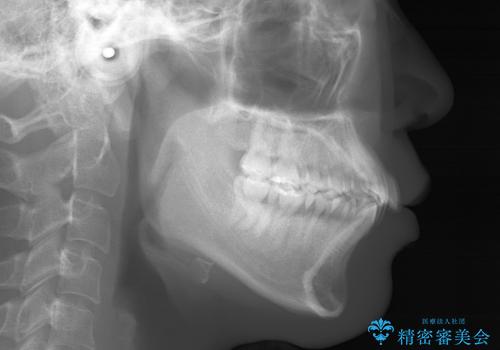

- 20代 女性

- ワイヤー(片顎舌側装置)

- 2年8ヶ月

- 治療計画

- 歯のガタつきと出っ歯感を治したいとの主訴でご来院され、ハーフリンガル装置を希望なさったため、検査を行ったうえで上下左右4番目の歯を抜歯し歯列を内側に引っ込めつつ叢生の改善を行うこととなりました。